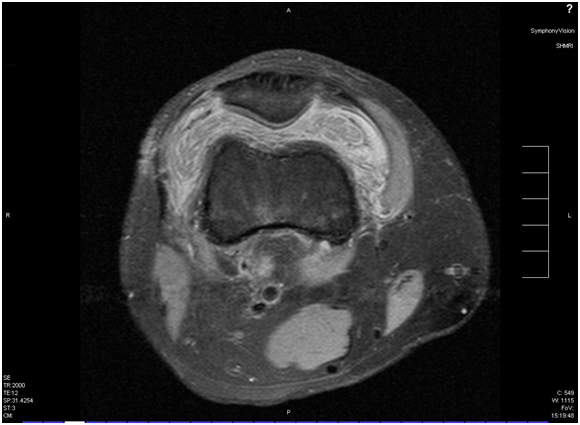

A 24-year-old white male sustained a right medial meniscal tear and anterior cruciate ligament (ACL) injury in January 2006. He was wrestling with some friends over a hard surface (concrete), when he sustained a twisting type injury to his right knee and felt a pop. He underwent a right arthroscopy for ACL reconstruction with a bone-tendon-bone cadaveric ACL allograft on September 16th, 2006. We could not determine information on antibiotic prophylaxis. His rehabilitation was unremarkable until January 2007, when he developed pain in his right knee, a new pop on his knee, with progressive swelling and joint effusion. He received a trial of physical therapy and nonsteroidal anti-inflammatory drugs (NSAIDs), with no resolution. He was evaluated by his orthopedic surgeon, who performed an arthrocentesis, relieving the swelling and pain. The fluid was not cultured. However, the swelling and the pain came back. Two more arthrocentesis were performed on February 5th and 15th. Both cultures from synovial fluid recovered Candida glabrata, which was believed to be responsible for his effusion and knee pain (cell count and differential were not available). He was started on IV caspofungin (loading dose: 70mg, maintenance: 50mg IV every day), with persistent swelling, pain with constant range of motion, and instability in his knee. He denied any numbness or tingling of the leg. He denied any other aches, bumps, and bruises. He also denied any current fever, chills or night sweats. His past medical history is unremarkable. He was not taking any medication in addition to caspofungin. He did not have any allergic reactions. He worked as a welder. He smokes two to three cigarettes per day, and denied alcohol or intravenous drug use (IVDU). His physical examination revealed a well-developed white male in no acute distress. His right lower extremity revealed a moderate effusion of the right knee, with considerable soft tissue swelling and mildly warmer than the left knee. Range of motion was from full extension to approximately 115 degrees flexion. The knee has a positive Lachman sign, the McMurray test was difficult to assess, and muscle strength was normal. He had a brisk capillary refill, and conserved sensation to light touch throughout his extremities. Surgical incisions from previous arthrocentesis did not show evidence of infection. Except for mild thrombocytosis (platelet count: 430x106/mL), complete blood count and basic chemistry were within normal limits. Erythrocyte sedimentation rate was 35mm, and C-reactive protein was 2.5mg/dL. An MRI showed a chronically ruptured ACL graft, with resorption of the graft, proximal retention screws extending into the joint space, and joint effusion (Figures 1-3). X-ray imaging showed osteolysis at the level of the tibial tunnel. An Infectious Diseases consultation was obtained, after concern for C.glabrata septic arthritis and possible osteomyelitis. Caspofungin was continued, and a new arthrocentesis was performed (cell count or differential were not performed).

Figure 3 Large effusion with multiple loose bodies on suprapatellar pouch and septum formation. Tibial tunnel with surrounding edema in bone is seen.